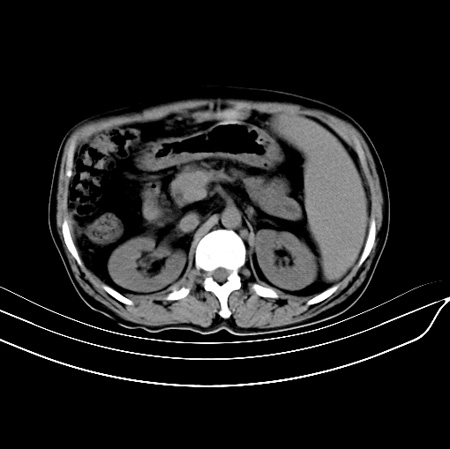

以下是引用江尾海头在2007-9-7 19:01:00的发言:[br]肝叶比例失调,肝边缘高低不平,尾状叶增大,肝裂增宽。肝右叶见较大密度减低影,边缘欠清。脾脏明显增大,胃底及奇静脉半奇静脉曲张。胆囊未见明显显示。 考虑:1、肝癌。2、肝硬化伴脾大静脉曲张。

以下是引用zhangxu5888在2007-9-7 22:31:00的发言:[br]1、肝硬化,食管 胃底及奇静脉半奇静脉曲张;2、脾脏肿大; 3、肝右叶的病灶呈锲性改变,内可见条片状钙化,边界清晰,密度明显低于周围正常肝组织,我觉得肝癌可能性不是很大, 同意楼上观点,有可能是栓塞,建议增强.